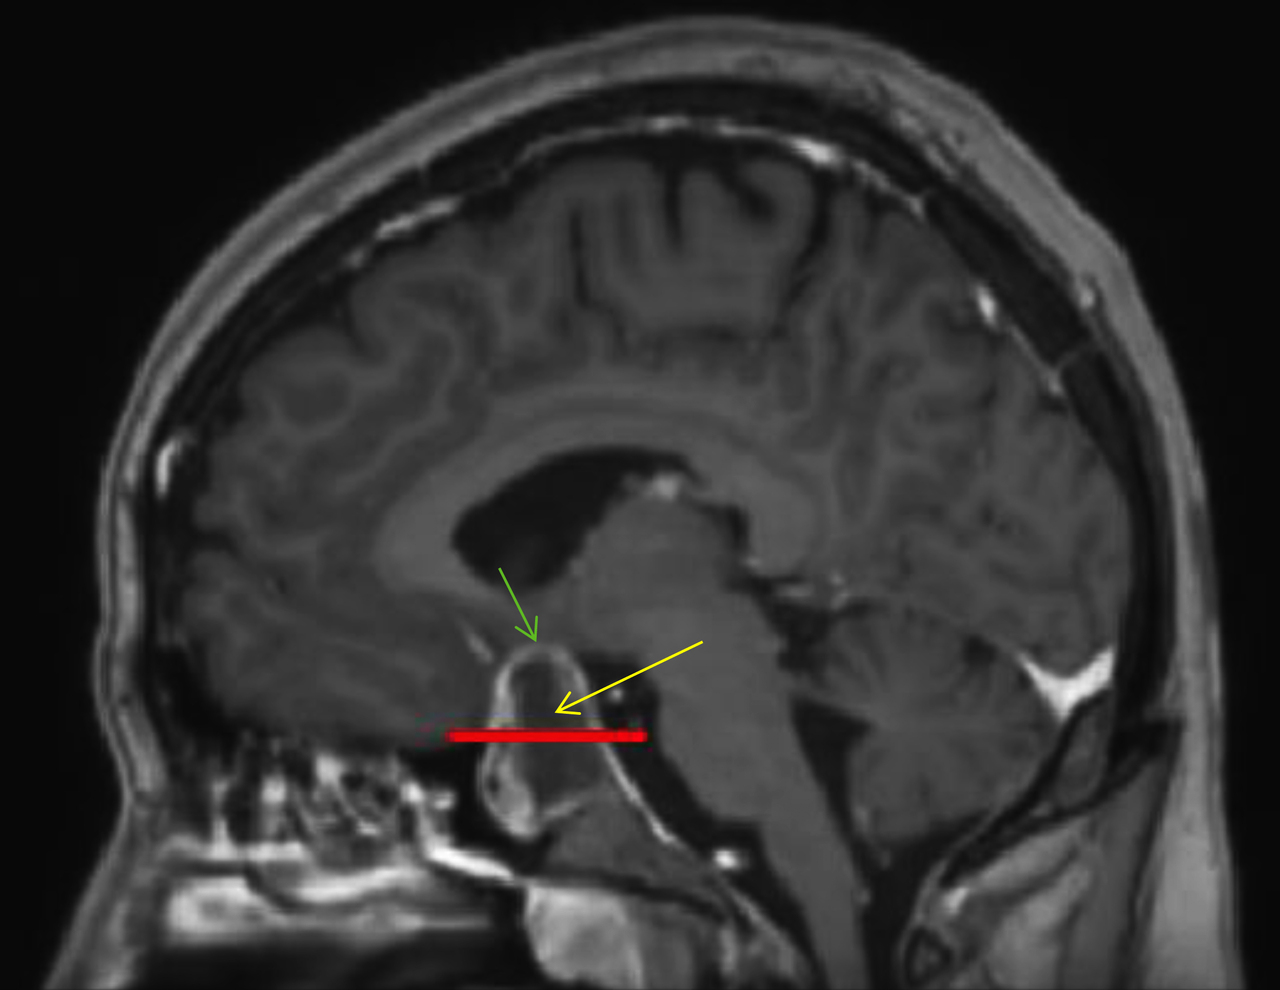

Le patient bénéficie également d’une imagerie par résonance magnétique (IRM) cérébrale devant un doute sur le scanner. Voici deux coupes (figures 2 et 3) :

Figure 3 (source : G. Kielwasser)

Figure 3 bis (source : G. Kielwasser)

Sur cette coupe sagittale en T1 avec injection de gadolinium (figure 3 bis), on observe les mêmes structures que sur la coupe précédente, avec la flèche jaune pointant le macroadénome hypophysaire hémorragique et la ligne rouge représentant la limite virtuelle de la loge pituitaire. La flèche verte pointe le chiasma optique comprimé par la masse.